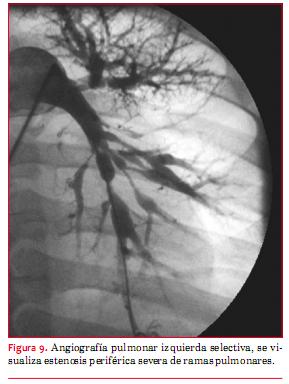

a. Estenosis de ramas de la arteria pulmonar

La dilatación con balón con o sin implante de stent es considerada como clase I en pacientes con estenosis de rama proximal o periférica con un diámetro menor a 50%, que tengan aumentada la presión de ventrículo derecho a más de 50 mmHg o síntomas. La estenosis de rama de la arteria pulmonar es una patología común, típicamente asociada a otras malformaciones como la tetralogía de Fallot y otras anomalías conotroncales, pero también puede ocurrir aislada. En estos casos, si se trata de estenosis periféricas en el adulto (figura 9), mimetiza la presentación del tromboembolismo pulmonar crónico, manifestándose con hipertensión ventricular derecha y defectos segmentarios de la perfusión en la centellografía pulmonar(26). Se dispone de una gran variedad de balones y stents que ayudan a lograr un alto éxito del procedimiento (más de 90%), incluyendo balones de alta presión, ultra-alta presión y balones de corte (figuras 10, 11a y 11b). Sin embargo, siguen existiendo lesiones resistentes a todas las técnicas.